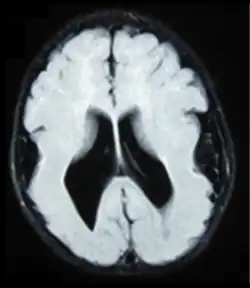

- Radiological findings (MRI) demonstrated symmetric generalized polymicrogyria with decreasing anterior-posterior gradient, most prominent in frontoparietal cortex.[5]

- Numerous gyrus on the cortex

- Small gyri and sulci

- Thin cortex

There are different tests or methods used to determine GPR56 expression or visuals of the brain to analyze the specific sections that are affected. These tests for example, using animals such as mice, RNAi, Behavioral assay, Electron microscopy, CT scan, or MRI demonstrate different results that concludes an affected BFPP patient.[15] MRI's reveal either irregularity to the cortical surface suggestive of multiple small folds or an irregular, scalloped appearance of the gray matter-white matter junction.

Neuroimaging

The diagnosis of polymicrogyria is typically made by magnetic resonance imaging (MRI) since computed tomography (CT) and other imaging methods generally do not have high enough resolution or adequate contrast to identify the small folds that define the condition. The cerebral cortex often appears abnormally thick as well because the multiple small gyri are fused, infolded, and superimposed in appearance.[5]